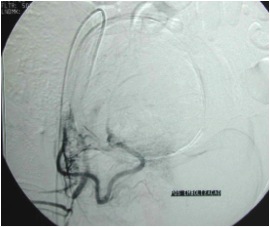

Embolização de miomas, também conhecida como embolização das artérias uterinas, é realizada por um radiologista intervencionista, um médico que é treinado para realizar este e outros tipos de embolização e procedimentos minimamente invasivos. Ela é realizada enquanto o paciente está consciente, mas sedado e não sentindo dor. Não requer anestesia geral.

O procedimento é realizado através de punção e inserção de um cateter na artéria femoral (artéria situada na virilha). Usando imagem digitalizada em tempo real, o médico guia o cateter pela rede arterial até posicioná-lo diretamente no vaso sanguíneo responsável pela irrigação (nutrição) do mioma. Em seguida, são liberadas microesferas que seguem o fluxo sanguíneo até atingir o tumor. Isto bloqueia o fluxo sanguíneo para o tumor mioma provocando morte das células e, consequentemente, encolhimento do mioma.